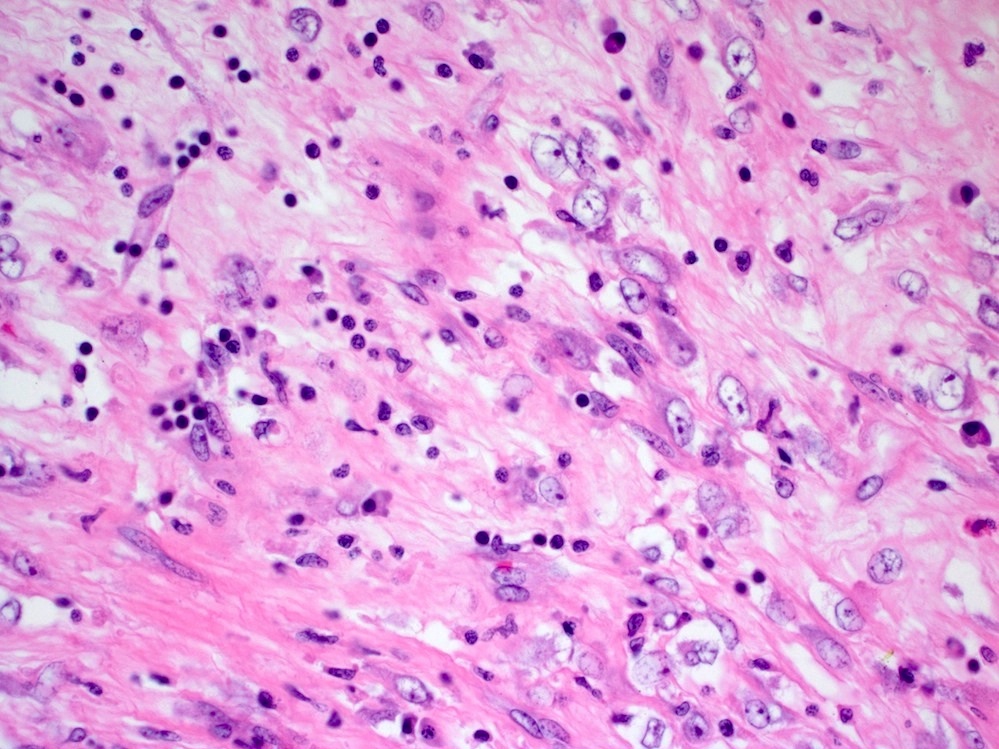

Microscopic (histologic) description

- Bland spindle cells with abundant amphophilic cytoplasm and variably prominent nucleoli

- Lymphoplasmacytic infiltrate with polyclonal plasma cells

- Background may show myxoid change or laminated / whorled fibrosis

- Epithelioid inflammatory myofibroblastic sarcoma: similar, except cells are more epithelioid, with large nucleoli

Microscopic (histologic) images

Contributed by Michael Feely, D.O.

A young male patient presents with abdominal pain. Imaging reveals a large mesenteric mass, which is resected. An image of the tumor’s histology is seen above. Immunohistochemistry shows ALK1 staining of the nuclear membranes. What molecular abnormality is present in this tumor?

C. t(2;2) RANBP2-ALK translocation. This is an epithelioid inflammatory myofibroblastic sarcoma.